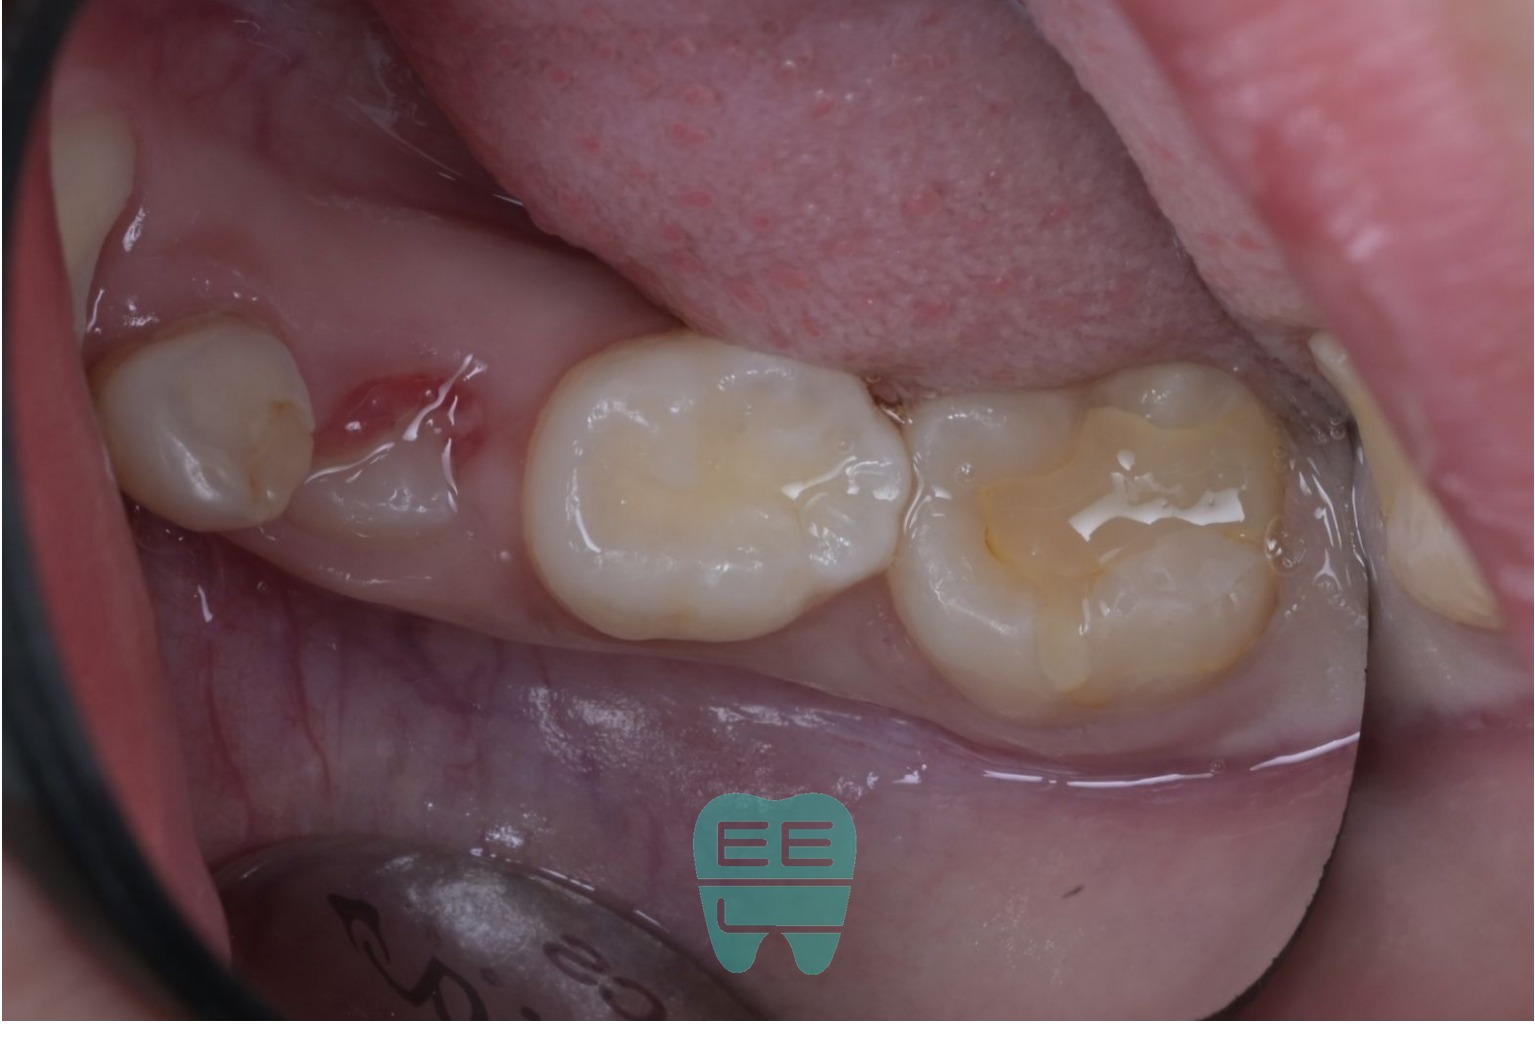

1. 초진 상태: 겉보기엔 괜찮아 보이지만...

처음 오셨을 때의 모습입니다. 언뜻 보면 레진 치료가 되어 있어 괜찮아 보입니다. 하지만 자세히 보면 기존 레진이 들떠있는 상태였습니다.